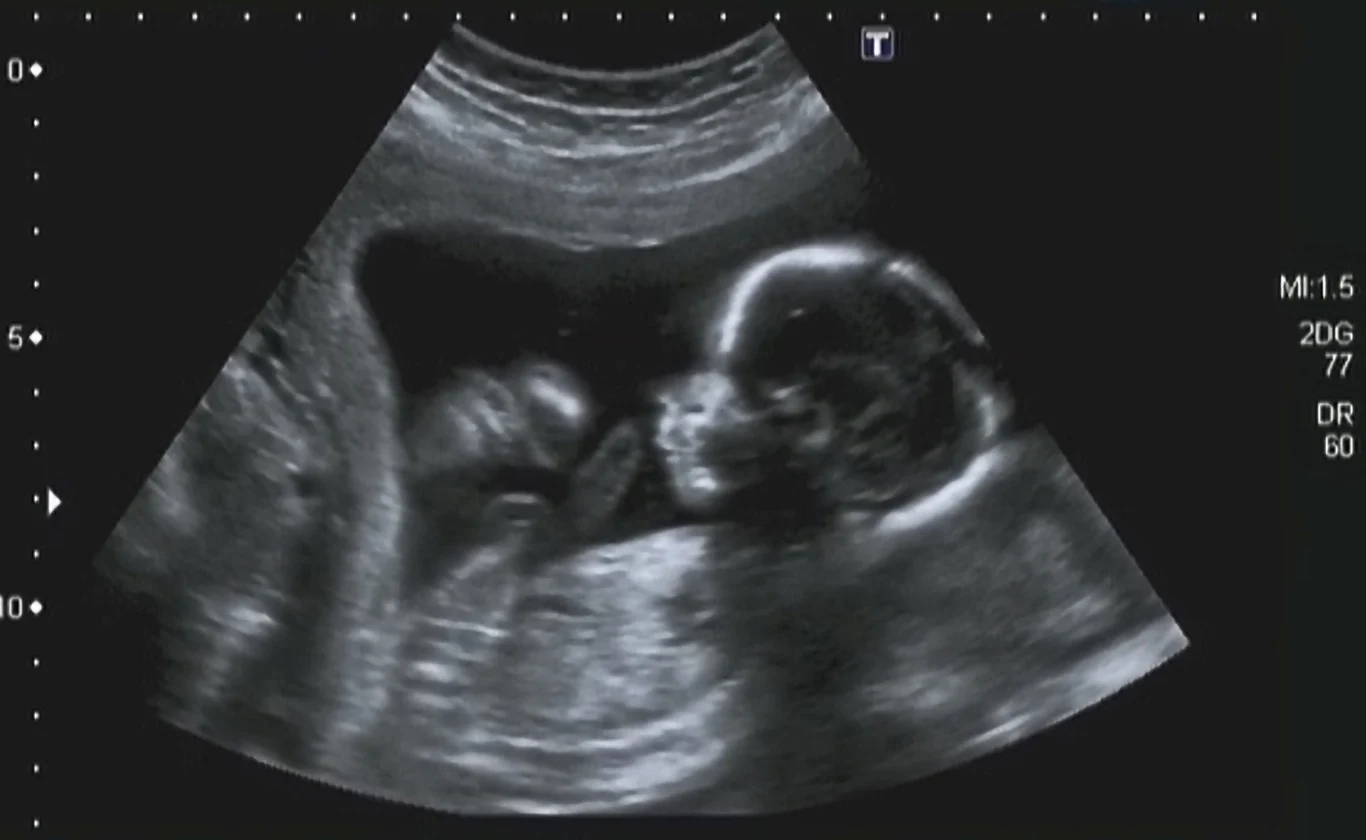

Zespół Edwardsa jest możliwy do wykrycia już na etapie końcówki pierwszego trymetru ciąży. Z pomocą przychodzą badania prenatalne, szczególnie tzw. USG genetyczne, wykonywane około 12. tygodnia ciąży, ukazujące odstępstwa od normy w budowie ciała dziecka. Ewentualne nieprawidłowości, które wykaże USG, są następnie potwierdzane przez badania inwazyjne.